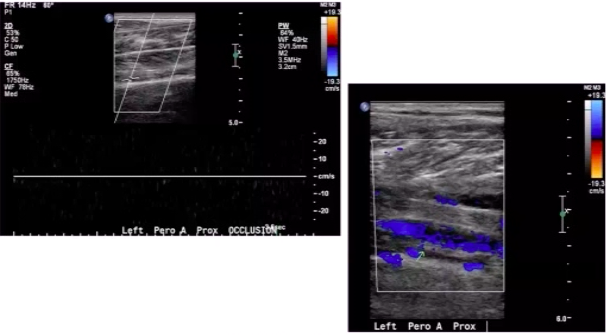

Pt undergoes LE arterial DUS. Interrogation of proximal peroneal artery is shown below.

Most important finding to report?

100% occlusion of proximal peroneal artery